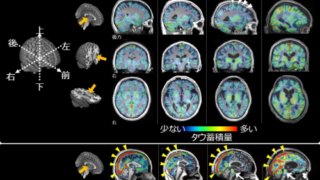

Nested sleep oscillations, emerging from asynchronous states in coordinated bursts, are critical for memory consolidation. Whether these bursts emerge intrinsically or from an underlying rhythm is unknown. Here, we show a previously undescribed respiratory-driven oscillation in the human hippocampus that couples with cardinal sleep oscillations. Further, breathing promotes nesting of ripples in slow oscillations, together suggesting that respiration acts as an intrinsic rhythm to coordinate synchronization of sleep oscillations, providing a unique framework to characterize sleep-related respiratory and memory processes.